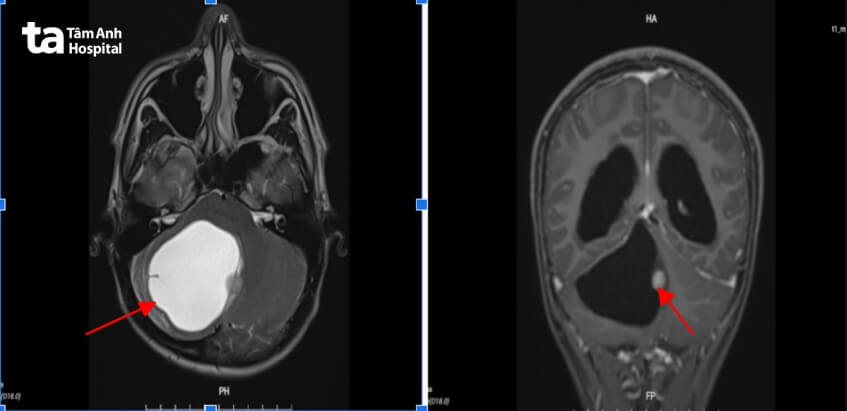

Ngày 23/4, ThS.BS.CK2 Chu Tấn Sĩ, Trưởng Khoa Phẫu thuật Thần kinh, Trung tâm Khoa học Thần kinh, Bệnh viện Tâm Anh TP HCM cho biết Nam nhập viện trong tình trạng mất thăng bằng, khó ăn, rung giật nhãn cầu, ghi nhớ khó khăn. Sau khi thăm khám và chụp MRI 3 Tesla, kết quả cho thấy một khối u lớn tương đương quả trứng vịt (đường kính hơn 6 cm), nằm ở hố sau vùng tiểu não, ngay sát bán cầu tiểu não phải.

Đây là u sao bào lông dạng nang độ thấp nhưng kích thước lớn với 90% là nang nước, còn lại là nhân u. Khối u choán gần hết phần hố sau vùng chẩm (vùng bán cầu vỏ não thị giác).

Bác sĩ Tấn Sĩ đánh giá khối u lớn và nằm ở vùng nguy hiểm, chỉ định mổ sớm để loại bỏ u, hồi phục các chức năng thần kinh cho Nam, đặc biệt là sức nhìn và tầm nhìn.